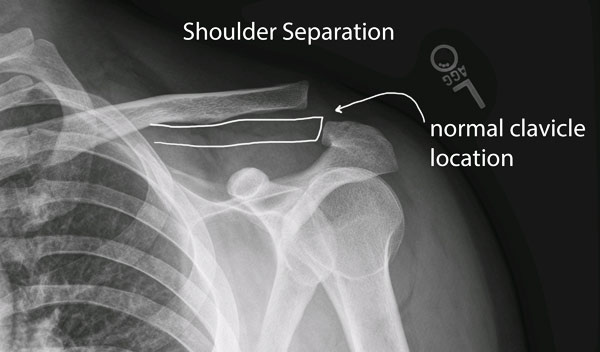

These injuries typically occur after a sudden fall onto the shoulder. Ac joint inflammation causes pain on the top of the shoulder, at the point where the collarbone (clavicle) meets the highest point of the shoulder blade (acromion). The acromioclavicular joint is located in the shoulder, the joint that connects the collarbone also called the clavicle the upper section of the shoulder blade known as the acromion.

These injuries typically occur after a sudden fall onto the shoulder. Ac joint pain due to injury. Shoulder pain ac joint pain , shoulder pain.